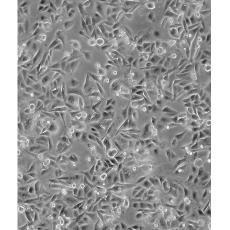

SW480 [SW-480]

中文名稱 人結腸癌細胞

組織來源 結腸腺癌;男性

生長特性 adherent

形態特征 epithelial

細胞描述 SW480取自ATCCCCL-227同一患者一年后的淋巴結轉移。CSAp和直腸抗體3陰性。角蛋白免疫過氧化物酶染色陽性。p53基因第273位密碼子的G->A突變導致Arg->His替代,309位密碼子的C->T突變導致Pro->Ser替代。細胞p53蛋白表達水平升高。致癌基因c-myc,K-ras,H-ras,N-ras,myb,sis和fos的表達呈陽性。未檢測到致癌基因N-myc的表達。不表達細胞溶解酶,一種與腫瘤入侵相關的金屬蛋白酶。有報道稱該細胞表達GM-CSF。